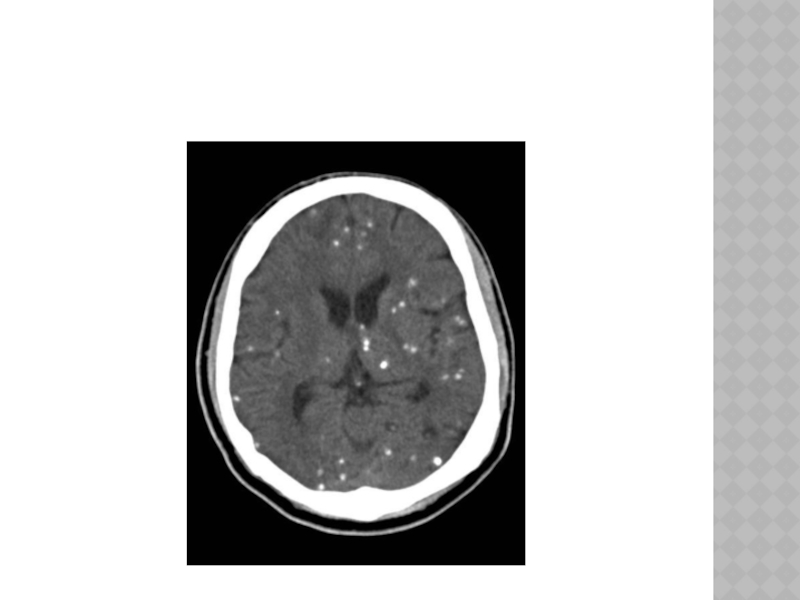

Слайд 137ЦИСТИЦЕРКОЗ ГОЛОВНОГО МОЗГА

-множественная гематогенная инвазия в мозг личинок свиного цепня.

-три

основные формы заболевания: 1).поражение больших полушарий(нарушения психики, мультифокальные эпилептические припадки, очаговые симптомамы, головные боли оболочечного характера), 2).поражение желудочковой системы(цистицеркоз желудочков мозга чаще бывает одиночным и локализуется в IV желудочке мозга, внутричерепная гипертензия, гидроцефалия боковых и III желудочков), 3).поражение основания мозга.

ЦИСТИЦЕРКОЗ ГОЛОВНОГО МОЗГА-множественная гематогенная инвазия в мозг личинок свиного цепня. -три основные формы заболевания: 1).поражение больших полушарий(нарушения